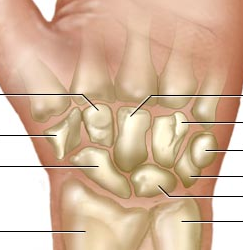

An ice skater tries her triple axle and fails, falling on an outstretch hand. She does not hear or feel anything break, but experiences sudden numbness along her thumb, index and middle fingers. What bone is likely causing these symptoms?

The lunate can dislocate and cause acute carpal tunnel syndrome.

A 28 year old female falls after tripping over a curb and hurts her hand. Upon examination she describes pain on palpation of the anatomical snuffbox. How quickly will she be able to heal from her injury?

The most likely injury here is a fracture to the scaphoid bone. This bone has a recurrent blood supply that gets broken off in a fracture and slows the healing process.